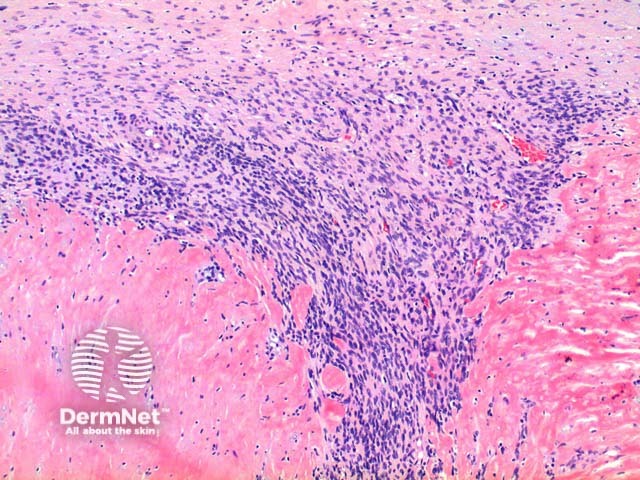

Low power view of myofibroma demonstrates a well defined multinodular tumour arising in the deep dermis or subcutis (Figure 1). Also at low power a branching ‘staghorn’ like pattern of blood vessels can be seen between the tumour nodules (Figure 2). Areas of calcification can often be seen (Figures 2, 3 and 5). The tumour nodules are comprised of a spindle cell proliferation with short plump nuclei (Figures 4,5 and 6). A basophilic tinge in the spindled peripheral component of the nodules is evident (Figures 7 and 8). Sclerotic collagen in the centre of the tumour nodules gives a biphasic appearance to the tumour (Figure 9).